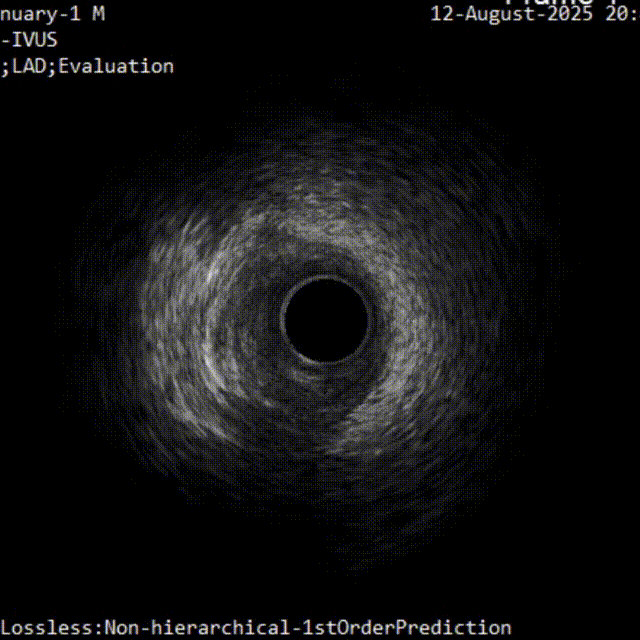

首先进行正向准备,对角支回撤IVUS明确CTO入口,Pilot200导丝进入

IVUS证实导丝进入CTO入口正确

从对角支回撤IVUS明确CTO入口,尝试对侧造影指导下采用正向导丝升级、平行导丝等技术进行正向开通,可通过对角支导丝送入IVUS指引CTO导丝“进攻”方向

(2)在实际操作过程中,冠脉CTA可以协助评估血管形态,导丝对吻、Knuckle技术、Carlino技术、导丝升级则可以帮助导丝前进,同时联合应用血管内超声检查可以明确管腔和导丝的位置关系。

③ 重视IVUS在CTO病变中的重要指导作用。